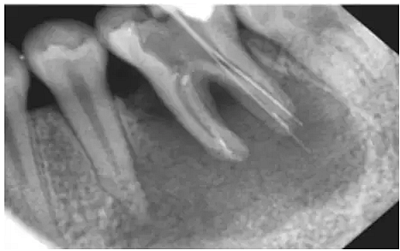

注:a.在鈣化細小/彎曲/形成臺階的根管,即使銼針未到狹窄區(qū),阻力也會明顯增大,導致感覺錯誤;b.在根尖周組織破壞嚴重(陰影部分),有痛感時,已明顯超出根管口。(如圖)

方法二:X光

采用X光拍片測量

優(yōu)點:能觀察牙的全貌,尤其是牙冠和牙根的解剖形態(tài),冠根關(guān)系以及牙根的大小、形態(tài)和位置

缺點:操作繁瑣、費事、射線污染

1) 三維結(jié)構(gòu)投射在二維平面上,因投射角度不一樣,數(shù)據(jù)容易出錯。

2)根尖孔不能體現(xiàn)在牙片上,而80%以上的根尖孔都不在牙齒根尖而是在側(cè)邊。

根尖開口在側(cè)邊時,X線片投射引起長度偏差錯誤。

根尖開口距離牙齒根尖距離越大,誤差越大,會引起嚴重超充。